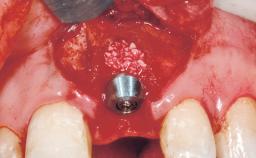

Immediate Flapless Placement of an Implant in a Maxillary Left Central Incisor Site

Bone Augmentation No

Soft Tissue Grafting None

Placement Protocol Immediate implant placement

Socket Integrity Damage to one or more bone walls

Bone Volume Damage to one or more socket walls